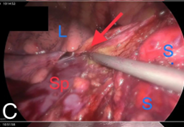

Congenital diaphragmatic hernia (CDH) is a birth defect involving improper formation of the diaphragm, leading to the protrusion of abdominal organs into the chest cavity. The CDH is classified depending on the location of the defect as postero-lateral, central and anterior. Depending on the side, it is classified as right, left and bilateral. A majority of CDH defects are postero-lateral defects and are commonly referred to as Bochdalek hernias (BH). Herein, the authors present the case of a 29 years old male patient diagnosed with a large left recurrent Bochdalek hernia. He was operated for it in another hospital by another surgeon 5 months back. That previous surgical intervention was initially planned via laparoscopy. But, intraoperatively, it had to be converted to open surgery due to technical difficulty. Post the first surgery, after about 1.5 months, he started developing pain in the back of his left chest. However, due to financial constraints, he did not seek any consultation with anyone at that time. The authors successfully performed a laparoscopic repair of this difficult condition. The rationale for reporting this case is to underscore the relative ease of a laparoscopic over open surgical intervention, on the ‘roof’ of the abdomen and also the lower chest. Also, it hopes to highlight that laparoscopic repair of BH is feasible even in challenging, difficult and recurrent scenarios, in an advanced setup backed up by the requisite surgical expertise.